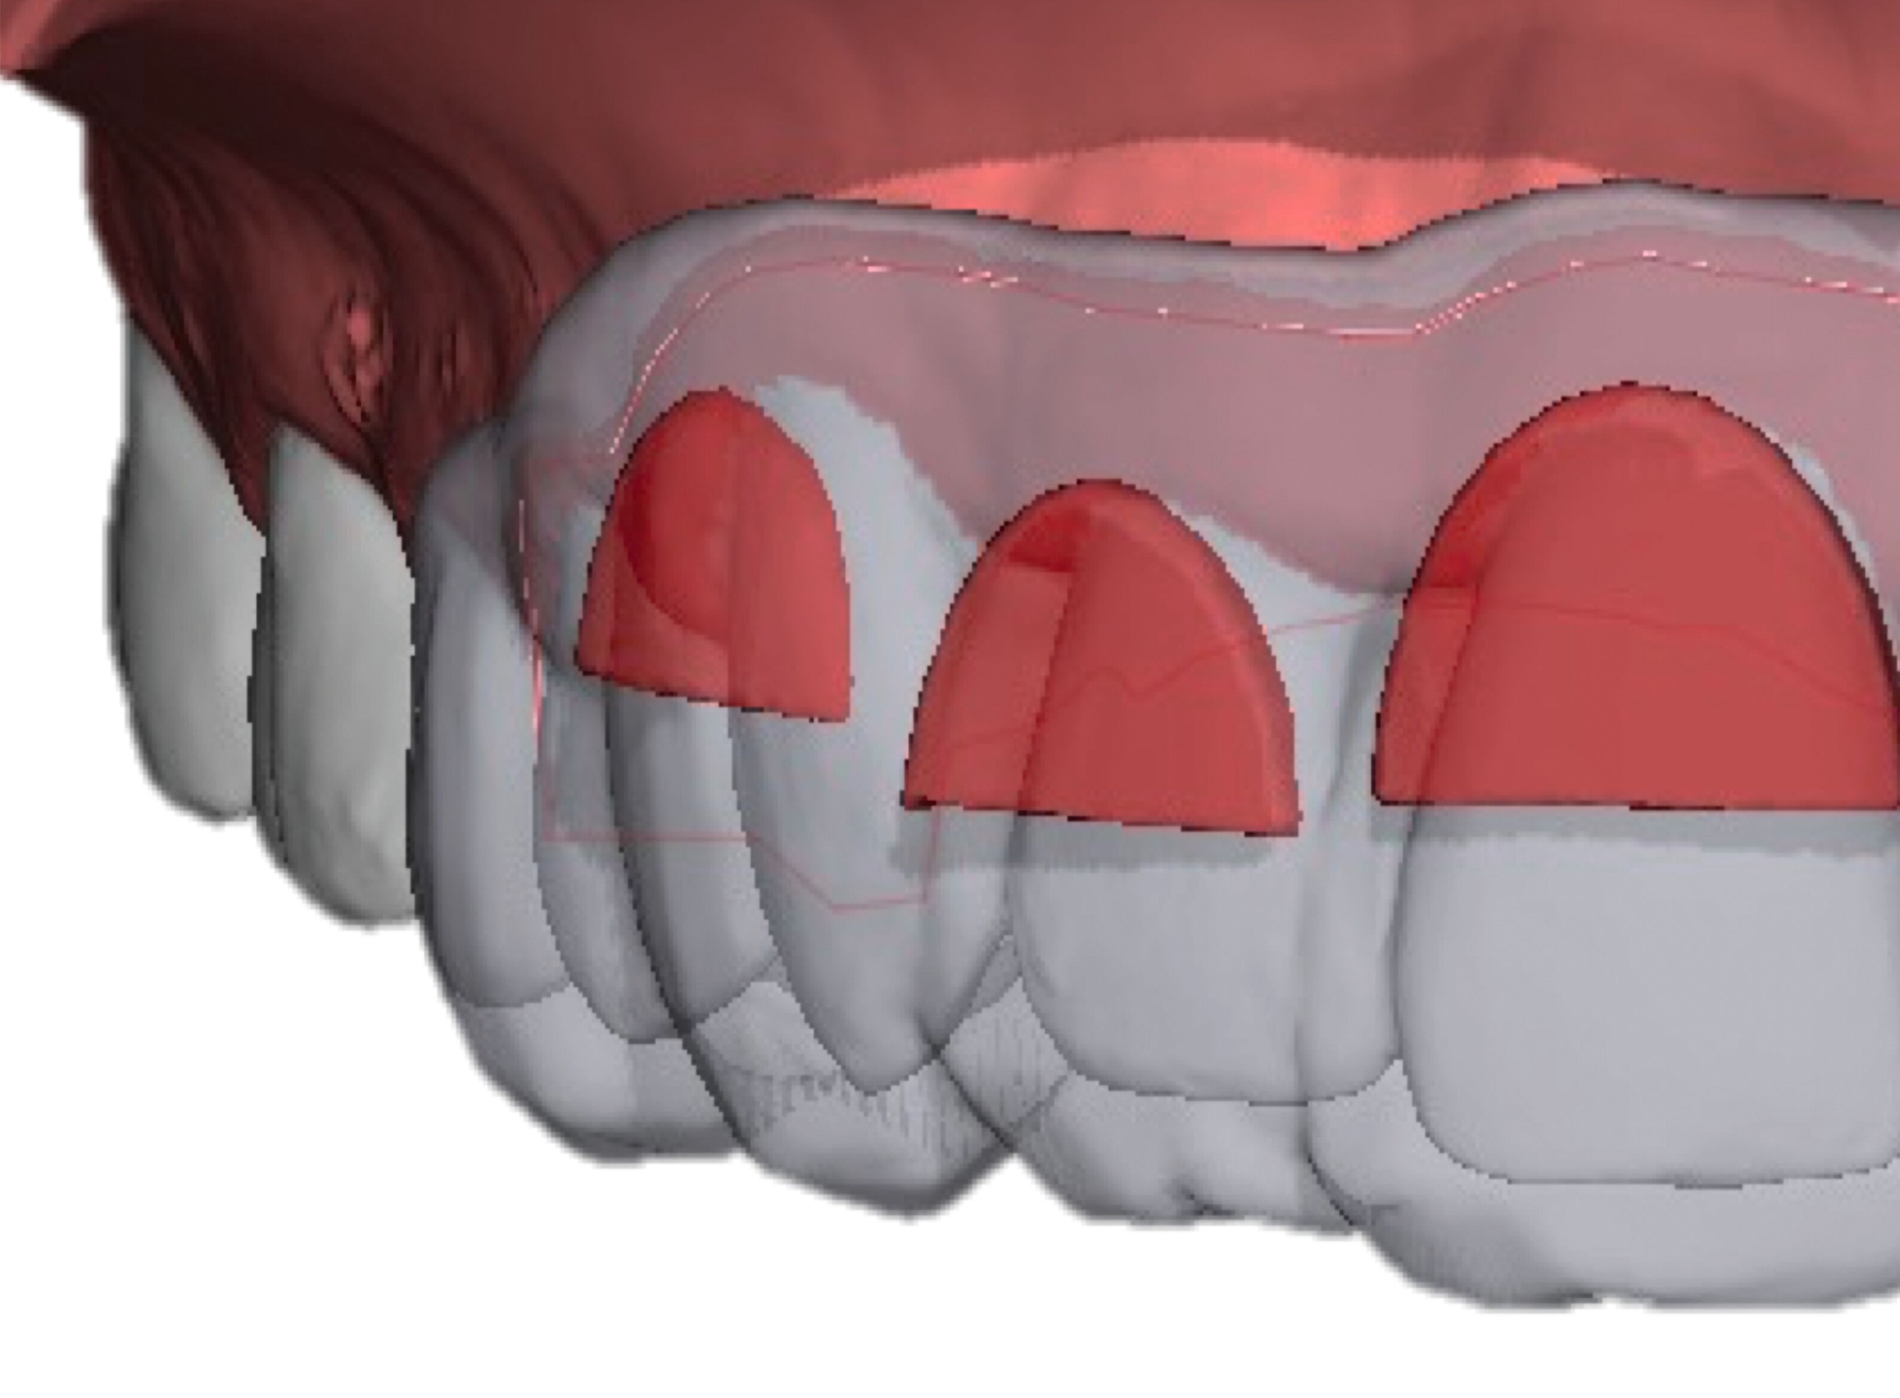

Anwendung findet der Metalldruck vor allem in der Herstellung skelettal verankerter Apparaturen, durch die reziproke Kräfte auf orthodontische Miniimplantate abgeleitet oder direkt skelettal aufgebracht werden können. Neben einer hohen Passgenauigkeit liegt der Vorteil vor allem in einer zielgerichteteren Therapie, die die anschließende oder zeitgleich durchgeführte Aligner- beziehungsweise Multibracket-Therapie verkürzt. Weiter können orthodontische Behandlungsaufgaben gelöst werden, die unter alleiniger Nutzung von Alignern beziehungsweise einer Multibracket-Apparatur deutlich limitiert wären. Beispiele beinhalten sogenannte „Mesialslider“ [Wilhelmy et al., 2022], „Distalslider“ [Graf et al., 2020] oder „Intrusionsapparaturen“.

Weiter erlauben hochindividuelle 3-D-gedruckte Designs die Therapie von skelettalen Fehlständen, beispielsweise in der Therapie defizitärer Maxillae [Pasqua et al., 2022; Bazargani et al., 2023; Ludwig et al., 2024] oder im Rahmen der nonoperativen oder postoperativen Prognathie-Behandlung [Hodecker et al., 2023]. Auch die Umsetzung skelettal verankerter Apparaturen mittels nichtmetallischer 3-D-Druckmaterialien findet in einzelnen Fällen Anwendung (Abbildung 3b). Zum Einbringen der Miniimplantate eignen sich sogenannte 3-D-gedruckte „Insertions-Guides“, die nach vorheriger digitaler Planung der Miniimplantat-Position, eine hochgenaue Insertion ermöglichen [Wilmes et al., 2022; Wilmes et al., 2022]. Die virtuelle Planung der Minischraubeninsertion ermöglicht eine sichere und nachvollziehbare Evaluation sämtlicher relevanter Gewebe, um die ohnehin geringen Risiken weiter zu minimieren. Zusätzlich kann man die Biomechanik der digital geplanten kieferorthopädischen Apparatur ideal koordinieren und – wenn man möchte – die Minischrauben und die Apparatur in einer Sitzung einsetzen.